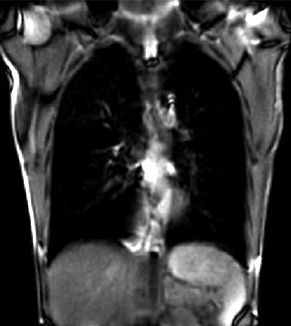

| fixed image/target | moving image |

| |

| unregistered moving series | moving input after registration (only frames 1-27 shown) |